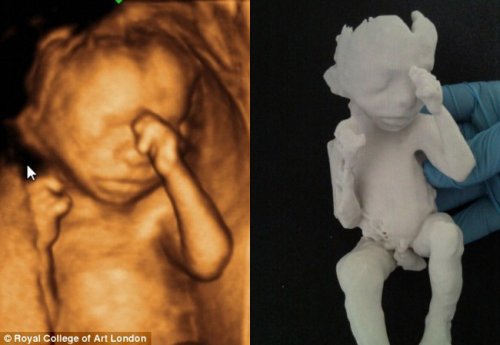

На 18-й неделе беременности происходят важные изменения в организме будущей мамы и в развитии плода. Малыш активно растет: его ручки и ножки уже сформированы, а фаланги пальчиков начинают приобретать очертания. Эта статья поможет понять, что происходит с ребенком на этом этапе, какие ощущения могут возникать у мамы и как поддерживать здоровье и комфорт. Мы также представим фотографии плода, чтобы вы могли визуально оценить, как выглядит ваш малыш на 18-й неделе.

На 18-й неделе беременности врачи отмечают значительные изменения в развитии плода. В этот период размер эмбриона достигает около 14 см, а вес составляет примерно 200 граммов. Врачи подчеркивают, что активно формируются внутренние органы, такие как печень и почки, которые начинают выполнять свои функции. Также на этой стадии развития плода происходит активный рост мышечной массы, что способствует улучшению координации движений.

Специалисты обращают внимание на то, что на 18-й неделе можно уже различить пол ребенка с помощью ультразвукового исследования. Это время, когда будущие родители начинают ощущать первые шевеления плода, что становится важным эмоциональным моментом для них. Врачи рекомендуют следить за своим состоянием, правильно питаться и избегать стрессов, чтобы обеспечить оптимальные условия для дальнейшего развития малыша.

Фото до 18 недель беременности:

На 18-й неделе беременности что происходит с вашим малышом? Ваш ребенок теперь примерно размером с батат или дыню, его длина составляет около 25 сантиметров, а вес — почти 300 граммов. Развитие вашего малыша близится к завершению, и его основная задача — активно расти.

На этом этапе беременности ваш малыш уже достаточно велик, чтобы вы могли ощущать его движения. Его кости становятся крепче! Кроме того, ваш ребенок может сосать пальцы, зевать и даже икать в утробе.

Нервная система вашего малыша также стремительно развивается. Нервы покрываются миелином — веществом, которое способствует более эффективной передаче сигналов между нервными клетками. Благодаря этому все пять чувств вашего ребенка уже функционируют. Его обоняние полностью сформировано, и теперь он может пробовать околоплодные воды, ощущать свет и слышать звуки вашего живота и ваш голос!

На 18-й неделе беременности: вместе с формированием отпечатков пальцев, половые органы вашего малыша почти полностью развиты. Если у вас девочка, то ее фаллопиевы трубы и матка уже на месте. Если это мальчик, вы сможете увидеть его пенис на следующем УЗИ, в зависимости от его положения.

Ниже 18 неделя беременности фото: